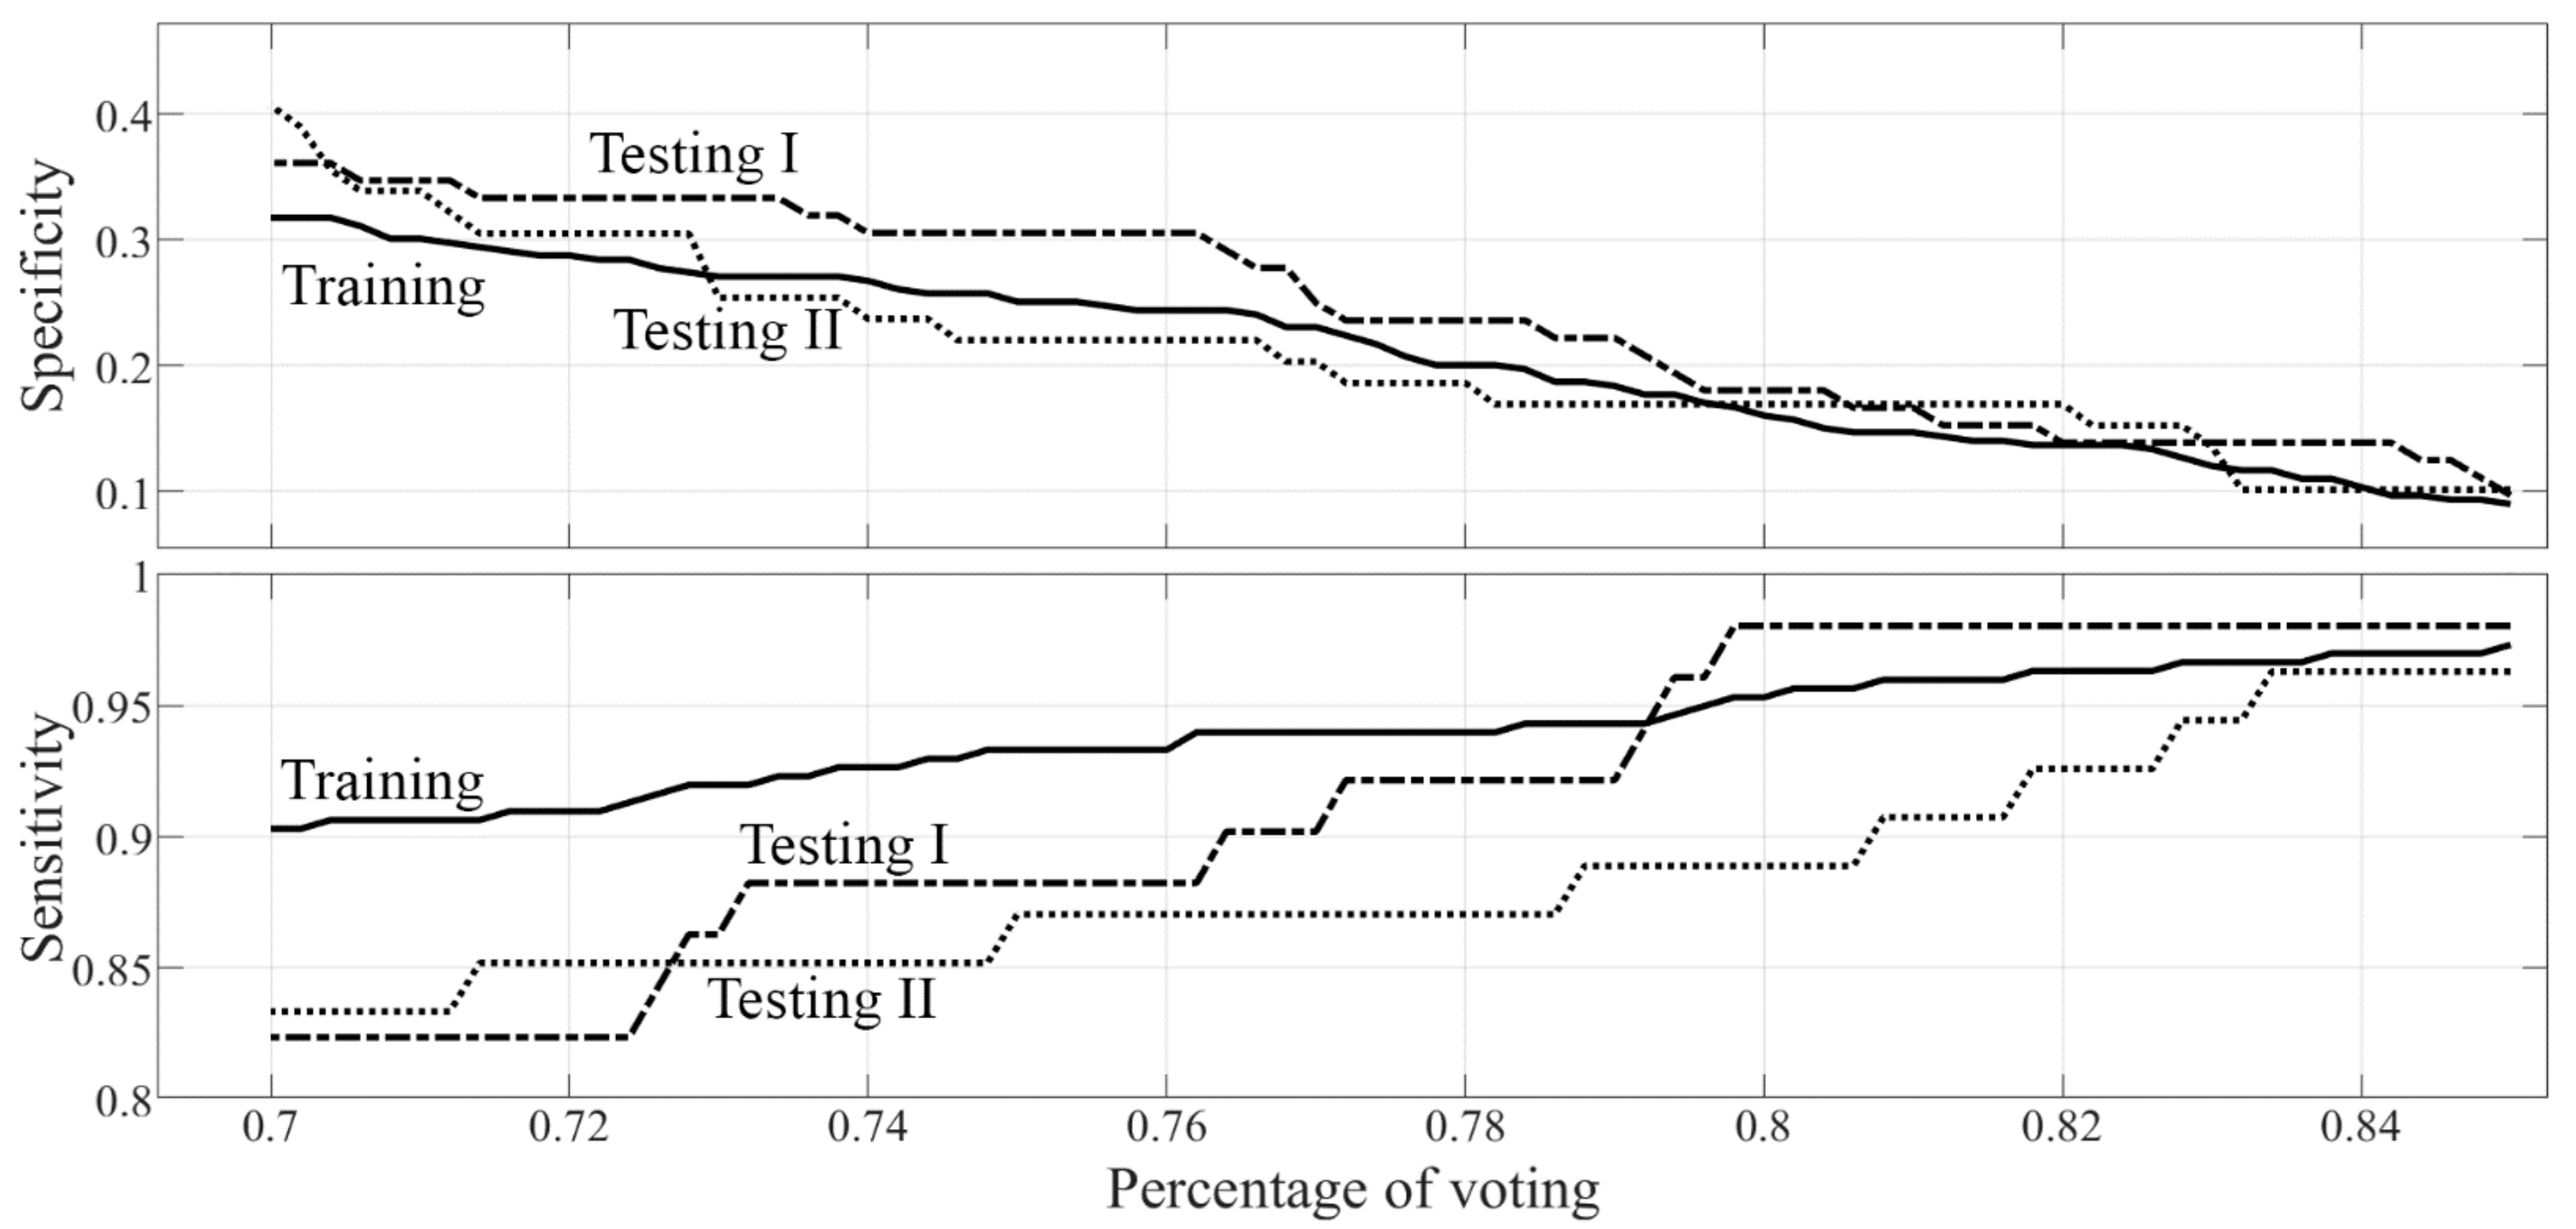

- Three different models of machine learning classifiers were trained, validated, and tested, for the binary classification task of interest (malignant versus benign discrimination), based on supervised learning, using histopathology as a reference standard. For each model, a nested k-fold cross-validation method was used (k = 10, 8 folds for training, 1 fold for tuning, 1 fold for hold-out testing, random sampling). The first model consisted of 3 ensembles of 100 random forest classifiers combined with Gini index with majority-vote rule; the second model consisted of 3 ensembles of 100 support vector machines (linear kernel) combined with principal components analysis and Fisher discriminant ratio with majority-vote rule; the third ensemble consisted of 3 ensembles of 100 k-nearest neighbor classifiers combined with principal components analysis and Fisher discriminant ratio with majority-vote rule. Data for the ensemble learning set were selected by using 100 baggings based on random sampling without replacement (80% data for training, 10% data for tuning, 10% data for internal testing). Each classifier belonging to the same ensemble was tested internally on datasets that can not have data samples in common. Classifiers belonging to different ensembles were tested on datasets that can have samples in common. The performances of the 3 models were measured across the different folds (k = 10) in terms of sensitivity, specificity, area under the receiver operating characteristic curve (ROC-AUC), positive predictive value (PPV), negative predictive value (NPV), and corresponding 95% confidence intervals (CI). The model with the best performance according to ROC-AUC was chosen as the best classification model for the binary task of interest (malignant versus benign discrimination).

3.2. Radiomic-Based Machine Learning Modelling

3.3. BI-RADS Diagnostic Categories Classification